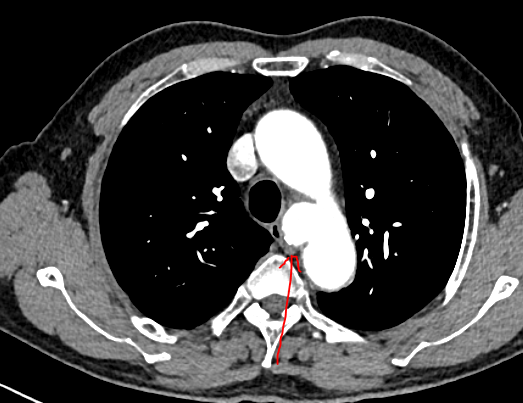

患者乔先生(化名)在查体时意外发现胸主动脉瘤,经主动脉CTA检查确诊后,医生发现其瘤体局部已出现先兆破裂迹象,随时可能发生破裂出血。要知道,胸主动脉是人体最大的动脉血管,堪称生命“主干道”,而胸主动脉瘤就像“体内的不定时炸弹”,一旦破裂,死亡率极高,救治刻不容缓。

一切准备就绪后,手术在全身麻醉下正式开展。手术团队凭借精湛的技术,经患者右侧股动脉穿刺,精准置入导丝及导管,在数字减影血管造影(DSA)的实时引导下,将覆膜支架系统精准输送至主动脉瘤病变部位,确认位置无误后,精准释放支架。整个手术过程精准、高效,仅用半小时便圆满完成。术后即刻造影显示,动脉瘤被完全隔绝,主动脉血流恢复通畅,无内漏、支架移位等异常情况,手术效果达到预期。